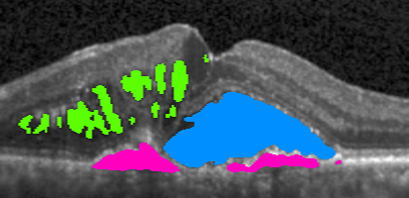

Input 666 121212 242424 Full Access Target

Refer to caption Refer to caption Refer to caption Refer to caption Refer to caption Refer to caption

Baseline

Our approach – Multi-label Deep Supervision

MIL Baseline

Deeply Supervised MIL

Our approach – Mean-Taught Deep Supervision

Figure 4: Segmentation progression when increasing the number of pixel-wise annotated masks from 666 to 121212, 242424, and full access. The upper two methods leverage only pixel-wise masks while the remaining three methods have access to weak annotations (image-level labels).

4.6 Qualitative results

In \figreffig:qualitative, we show segmentation results as more annotations are added for the Baseline and Multi-label Deep Supervision models as well as some semi-weakly supervised results. Comparing the first two rows, we observe the advantageous effect of our deep supervision technique, especially in the low-data setting. Similarly, when comparing our deep supervision in Mean-Taught models (bottom row) to the rest, we directly see in column two and three that our models nicely segment the fluid regions, even with extremely few samples while other methods fail severely.